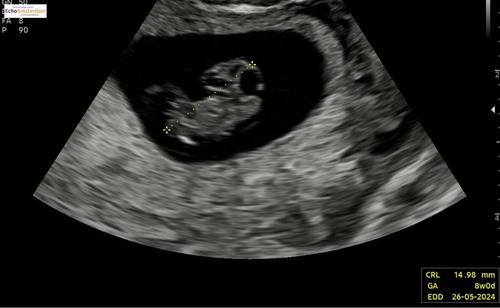

Deze was rond 8+4. Vroeger dan de vorige foto maar scherper beeld door ander echo apparaat!